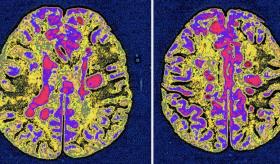

Esclerosis Múltiple - Infografía

Esta condición aún no cuenta con una cura, sin embargo, se pudo conocer que el virus de Epstein-Barr estaría relacionado con la aparición de la enfermedad: https://ow.ly/fABL50Hv8FP